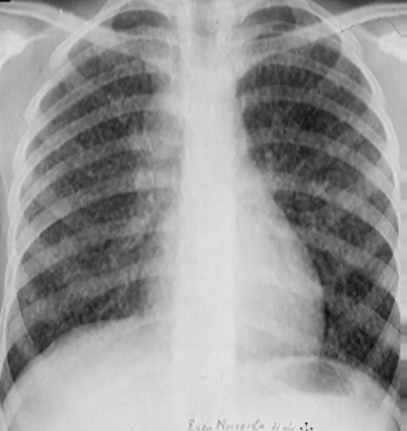

Rx toracică, incidență P-A

DESCRIERE:

pe tot teritoriul pulmonar, bilateral → opacități nodulare multiple de dimensiuni variabile, intensitate medie-mare, omogene, cu contur imprecis delim

confluente

distribuție anarhică

DX: bronhopneumonie

DD:

miliara TBC

MTS pulm hematogene